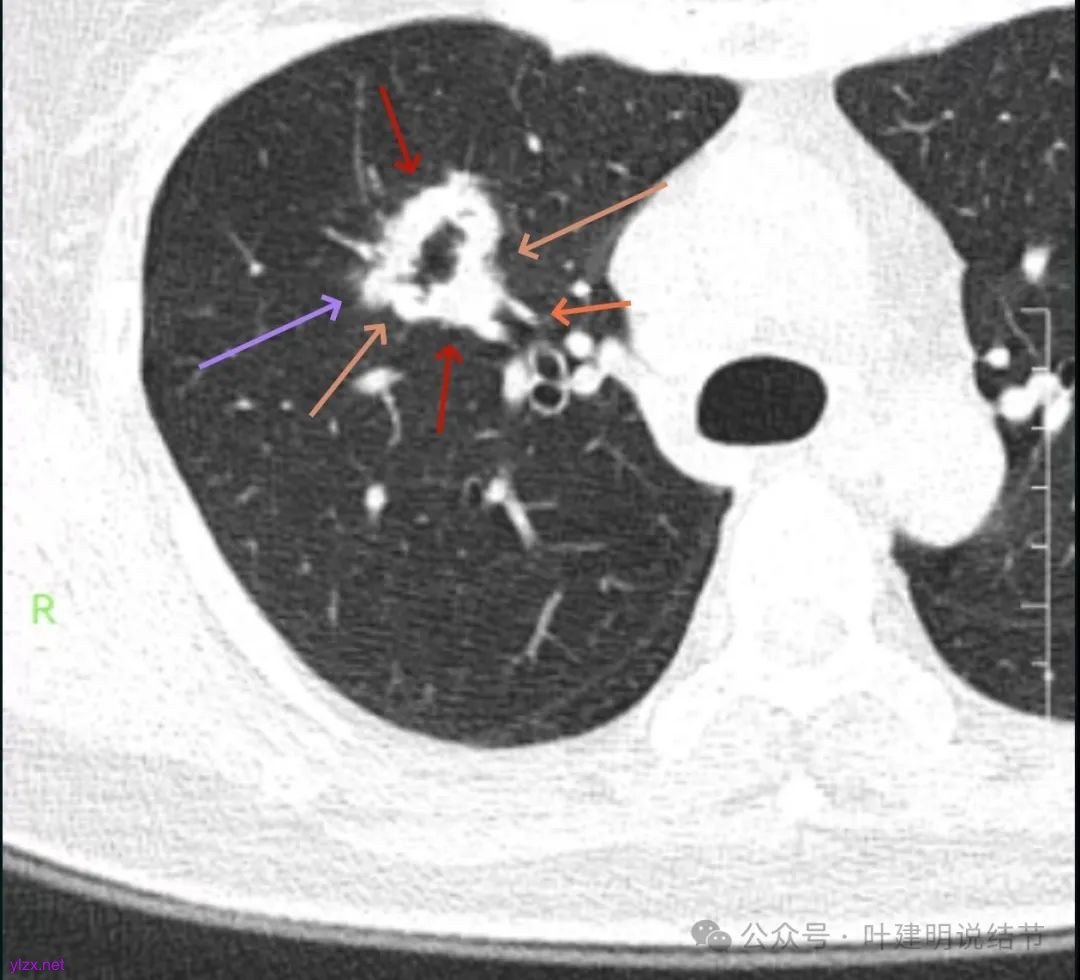

影像展示与分析:

你的右上叶这个病灶基本上肯定是肺癌,要尽快处理。从影像上看有以下特点:1、整体轮廓清楚,不似普通炎症的周围有晕或阻塞性改变;2、边缘明显的浅分叶,总体上的感觉膨胀性明显,不管哪个层面看上去都是鼓鼓的;3、边缘区域有磨玻璃成分而且也是分叶状的;4、部分层面见血管进入;5、空腔病灶的壁厚薄不均,内壁不光滑。我考虑中低分化肺癌,由于腔静脉旁有明显肿大淋巴结,需要进一步完善增强CT以及PET-CT检查以明确有无远处转移,是否仍可手术治疗(从病灶本身来说是可以肺叶切除治疗的)。要尽快处理。意见供参考!